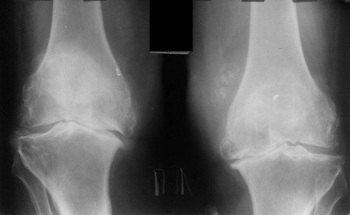

Endoproteza koljenskog zgloba, fotografija.